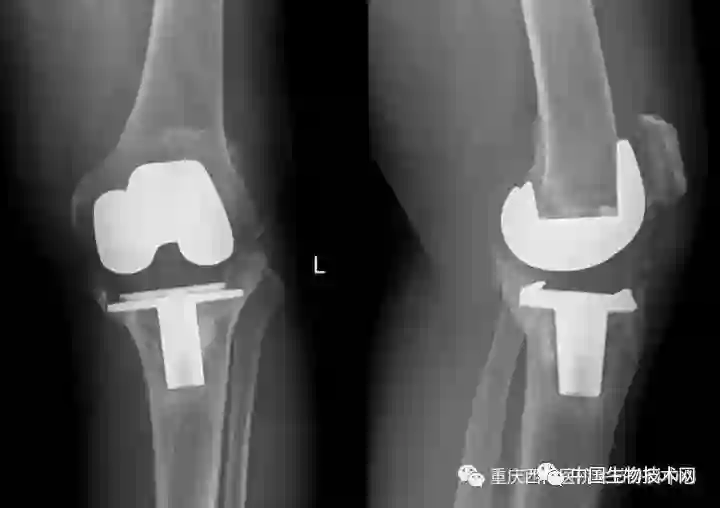

术前X光片

术后X光片